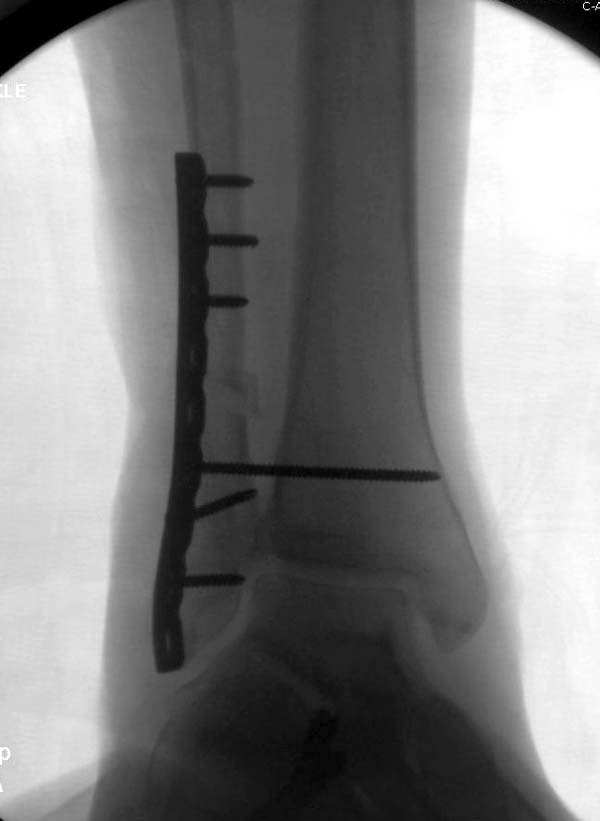

Проведена обычная стандартная процедура по исправлению неудовлетворительного состояния голеностопного сустава, где кроме удлинения малоберцовой с применением compression tension device за проксимальный конец пластины, проведено замещение трикортикальным графтом из крыла, освобождение синдесмоза и медиальной щели от

фибротических масс с фиксацией.